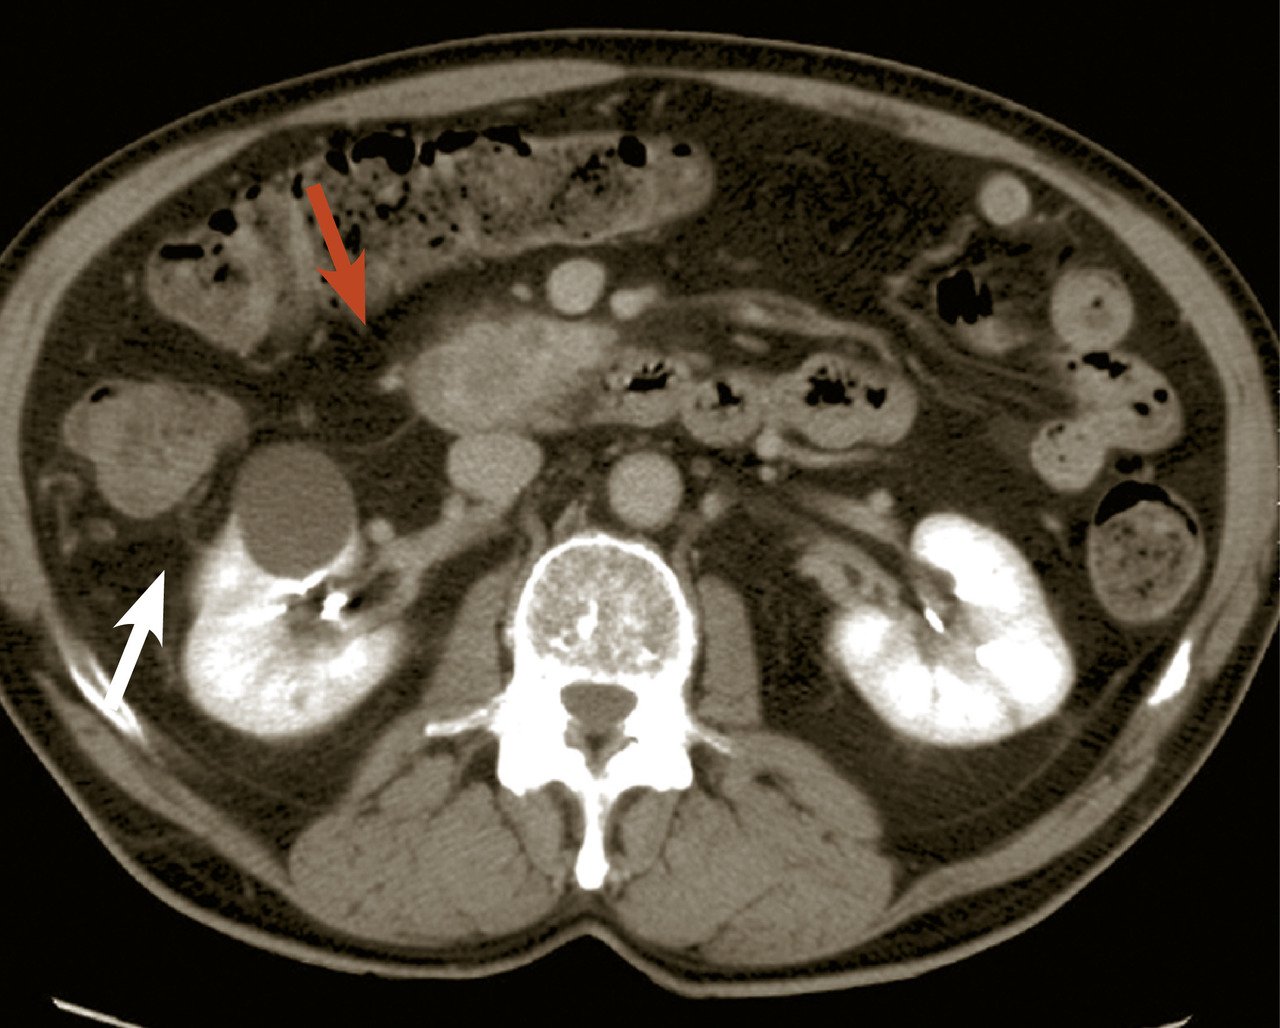

L’échographie abdominale a l’inconvénient d’être opérateur-­dépendante. Ses principales indications sont la lithiase biliaire et ses complications, des douleurs abdominales chez les patients minces et surtout chez la femme pour rechercher une pathologie gynécologique en utilisant le cas échéant des sondes endocavitaires. Ainsi, l’échographie est utile pour affirmer la lithiase biliaire et la cholécystite aiguë (fig. 1) ou objectiver une dilatation de la voie biliaire principale (VBP), rechercher une urétéro-hydronéphrose et des signes indirects en cas de colique néphrétique (fig. 2 et 3), débrouiller le diagnostic des douleurs abdomino-­pelviennes chez la femme.

Le scanner abdomino-pelvien, voire thoraco-abdomino-pelvien, avec si possible injection de produit de contraste iodé (absence de contre-indication, notamment allergie à l’iode, insuffisance rénale sévère et grossesse), s’est progressivement imposé comme moyen d’imagerie diagnostique de première intention grâce à sa précision anatomique, sa rapidité de réalisation, son efficacité diagnostique dans la plupart des tableaux abdominaux urgents à l’exception de la pathologie aiguë annexielle gynécologique. C’est l’examen de choix dans les pancréatites aiguës après 48 à 72 heures d’évolution (fig. 4). L’irradiation et la néphrotoxicité des produits de contraste iodé limitent une application encore plus large chez l’insuffisant rénal, l’enfant, et la femme en âge de procréer (dosage préalable des ß-hCG pour s’assurer de l’absence de grossesse en cours), chez lesquels l’imagerie par résonance magnétique (IRM) abdomino-pelvienne est particulièrement indiquée, mais souvent plus difficile à obtenir en urgence.

Le diagnostic est évoqué devant une violente douleur épigastrique transfixiante, soulagée partiellement par la flexion du tronc (position en « chien de fusil »), une élévation franche de la lipasémie (supérieure à trois fois la valeur normale) et l’imagerie caractéristique au scanner. Deux causes dominent : la migration d’une lithiase biliaire et l’alcoolisation. L’examen clinique est pauvre contrastant avec l’intensité de la douleur et la gravité des signes généraux (marbrures, polypnée, pouls filant, hypotension artérielle). Un premier score de Ranson (clinico-biologique) supérieur à 3 affirme la sévérité de l’épisode. Le scanner (fig. 4), idéalement réalisé après 48 heures, permettra le calcul du score de Balthazar, fortement prédictif d’une complication grave (sur­infection des coulées de nécrose ou décès), en cas de valeur ≥ 4.

L’échographie peut montrer une discrète asymétrie des cavités excrétrices rénales, voire l’obstacle lithiasique avec dilatation d’amont (fig. 2 et 3). L’uroscanner complète le bilan et localise si besoin le calcul. Outre le traitement de la cause (calcul, compression extrinsèque…), le traitement antalgique est primordial : anti-inflammatoires non stéroïdiens (AINS), paracétamol, anti­spasmodiques voire dérivés morphiniques. On procédera à la pose d’une sonde urétérale en cas d’anurie (rein unique), de fièvre sur rétention du haut appareil ou de crise hyperalgique.